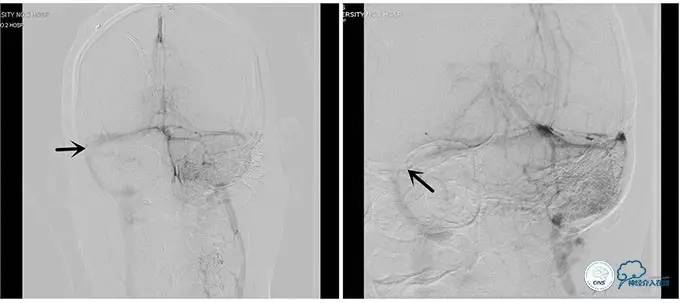

术中右侧ICA造影

右侧ICA斜位及窦内造影

右侧ICA斜位

窦内造影及路图

术中测压:

远端:520mmH2O,

近端:190mmH2O。

治疗方案:

1、8mm×40mm , EverCross球囊扩张;

2、8mm×40mm,Protégé自膨支架成形术。